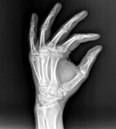

醫(yī)學(xué)影像學(xué)作為醫(yī)學(xué)專業(yè)大類中的一門(mén)重要學(xué)科,在醫(yī)學(xué)領(lǐng)域占有重要地位。學(xué)習(xí)醫(yī)學(xué)影像學(xué)具有以下特點(diǎn)。

1、實(shí)踐性強(qiáng)。學(xué)習(xí)影像學(xué)必需借助機(jī)器或膠片了解各種影像學(xué)檢查方法,學(xué)習(xí)必要的技術(shù)操作。應(yīng)重視每一個(gè)實(shí)訓(xùn)操作機(jī)會(huì),多動(dòng)腦多動(dòng)手,在老師指導(dǎo)下,掌握基本操作方法、程序和技能。

2、想象力強(qiáng)。醫(yī)學(xué)影像學(xué)是一門(mén)以圖像為基礎(chǔ)的專業(yè)課,學(xué)習(xí)過(guò)程中主要是通過(guò)觀察大量的圖片培養(yǎng)分析問(wèn)題、處理問(wèn)題的能力。學(xué)生必須學(xué)會(huì)對(duì)影像圖像的直觀認(rèn)識(shí)、三維空間思維,建立起各種影像間的立體聯(lián)系,可大大增強(qiáng)對(duì)疾病多方面影像的認(rèn)識(shí)能力。對(duì)將來(lái)閱讀CT、DSA(數(shù)字減影血管造影)、MRI片和超聲聲像圖大有裨益。

3、范疇廣泛。醫(yī)學(xué)影像學(xué)所涉及的臨床學(xué)科廣泛,涉汲檢查技術(shù)比較多,與人體解剖學(xué)、生理學(xué)、病理學(xué)、電子電工學(xué)、臨床醫(yī)學(xué)、醫(yī)學(xué)心理學(xué)等相關(guān)學(xué)科密切相關(guān)。只有學(xué)好本專業(yè)實(shí)際工作所必需的基礎(chǔ)醫(yī)學(xué)與臨床醫(yī)學(xué)的基本理論和基本知識(shí),掌握常見(jiàn)病、多發(fā)病的診療規(guī)律掌握醫(yī)學(xué)影像專業(yè)的基本理論和基本技能,才能在將來(lái)工作中正確應(yīng)用影像學(xué)檢查結(jié)果為臨床診斷和治療服務(wù)。